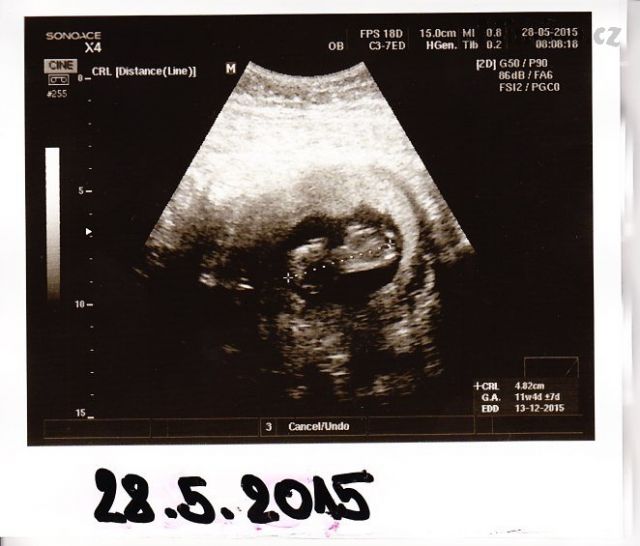

28. května 2015 (11+4)

– první miminko 11+6, 5,17cm

– druhé miminko 11+4, 4,82cm